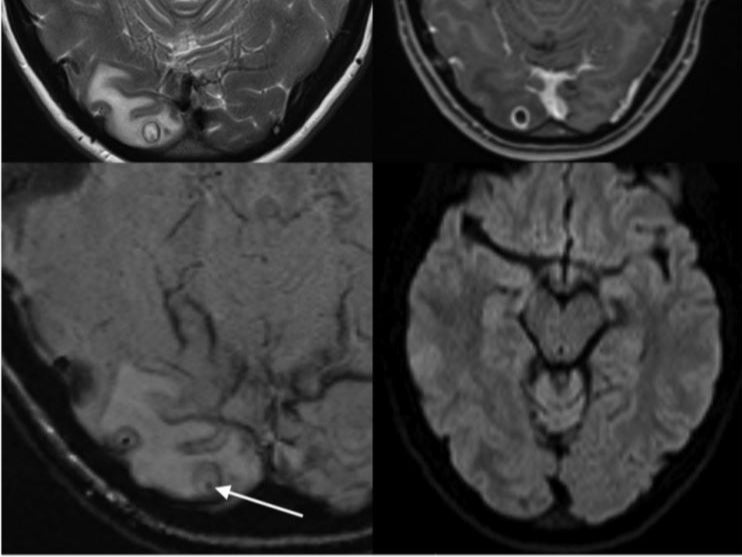

Scans that were carried out showed that she had a cyst-like tumor in her brain, and after operation and biopsy, they found out that it was a cyst that was full of tapeworm larvae.